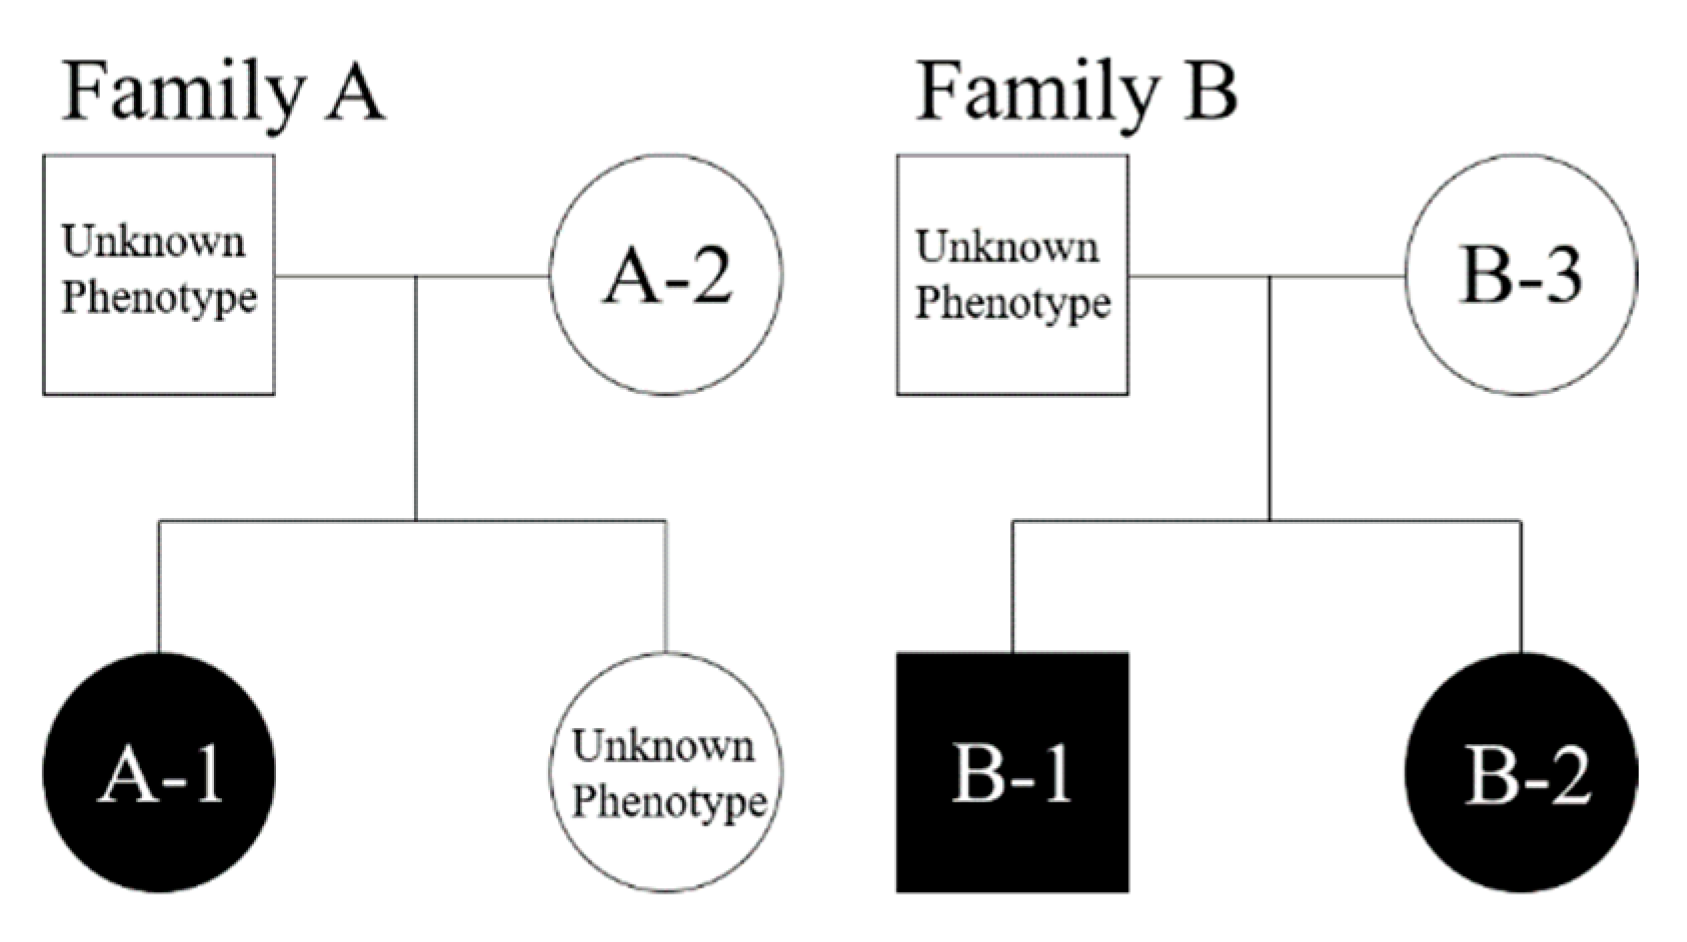

3.1. Clinical Findings

| Subject * | Sex | Dental Arch | Dens Evaginatus | Inclusion Type |

|---|---|---|---|---|

| A-1 | Female | Lower | Left and right first premolar, right second premolar | Bilateral |

| A-2 | Female | Lower | Left second premolar | Monolateral |

| B-1 | Male | Lower | Left and right first premolar | Bilateral |

| B-2 | Female | Lower | Left first premolar | Monolateral |

| B-3 | Female | - | - | - |